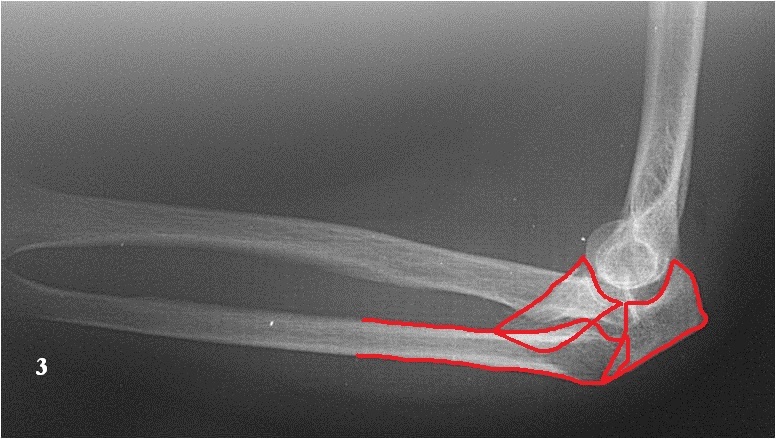

Хочу попросить совета у сообщества по поводу следующего клинического случая. Женщина, 65 лет. Закрытый перелом Монтеджи слева в октябре 2013 года. (рис. 1, 2). Для наглядности сделал скиаграмму перелома (рис. 3, 4). На 8-е сутки накостный остеосинтез пластинами с угловой стабильностью. Головка луча была восстановлена из отломков (рис. 5) и собрана на спицах одну из которых скусили и оставили под пластиной.(рис. 6). Вроде получилось стабильно, видео на операции по этой ссылке: